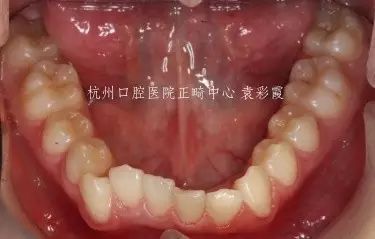

儿子

深覆合治疗前

戴上牙套